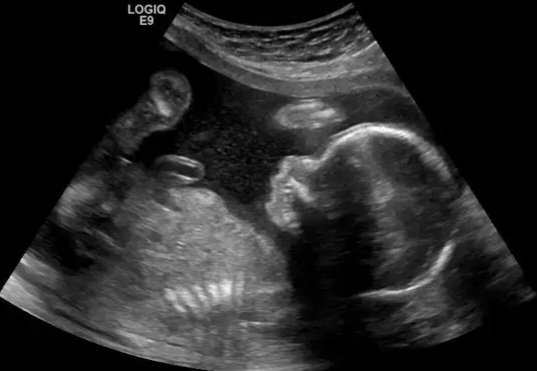

“All I wanted to know, quite simply, was whether these various masses of tissue differed in their ultrasonic echo characteristics. The results were beyond my wildest dreams…” Dr. Donald later wrote. He authored an article about his discoveries and included the first published sonogram image of a fetus.

By the 1970’s, ultrasounds were becoming a common tool used by doctors in obstetric care all over the world to determine the health and well-being of unborn babies and their mothers.

An ultrasound uses sound waves to produce images of bones, organs, tissue, and cysts that doctors can analyze in order to better treat their patients. It makes visible what before was invisible.